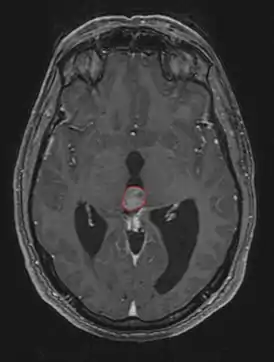

Симптомы опухоли обусловлены её расположением. Наиболее частыми симптомами являются головные боли, тошнота и рвота. Они обусловлены повышением внутричерепного давления вызванного обструктивной гидроцефалией, которая возникает при сдавлении опухолевой массой водопровода мозга и нарушением циркуляции спинномозговой жидкости.

Компрессия верхнего двухолмия опухолью приводит к синдрому Парино - невозможности вертикальных движений глаз, небольшой дилатации зрачка. Возможно развитие отёка соска зрительного нерва